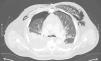

A 71-year-old male in the postoperative period of cardiac surgery presents with respiratory failure, severe hypoxemia, and predominantly left-sided subcutaneous emphysema, requiring re-intubation and 100% FiO2. A chest X-ray could not rule out bilateral pneumothorax. Additionally, he presents with significant hemodynamic instability requiring high doses of norepinephrine, and a distended, tympanic, and painful abdomen on examination, developing hyperlactacidemic acidosis. A CCTA performed confirms the presence of bilateral hydropneumothorax, mediastinal emphysema with involvement of the thoracic wall (Fig. 1), and at abdominal level, a distended bladder with a fluid-air level and atypical intraluminal air consistent with emphysematous cystitis of probable obstructive origin, with the Foley catheter distal end in the membranous urethra (Fig. 2). The Foley catheter was repositioned with the release of abundant gas, and a chest drain was placed. The patient showed progressive improvement with the resolution of emphysematous cystitis on follow-up CCTA.